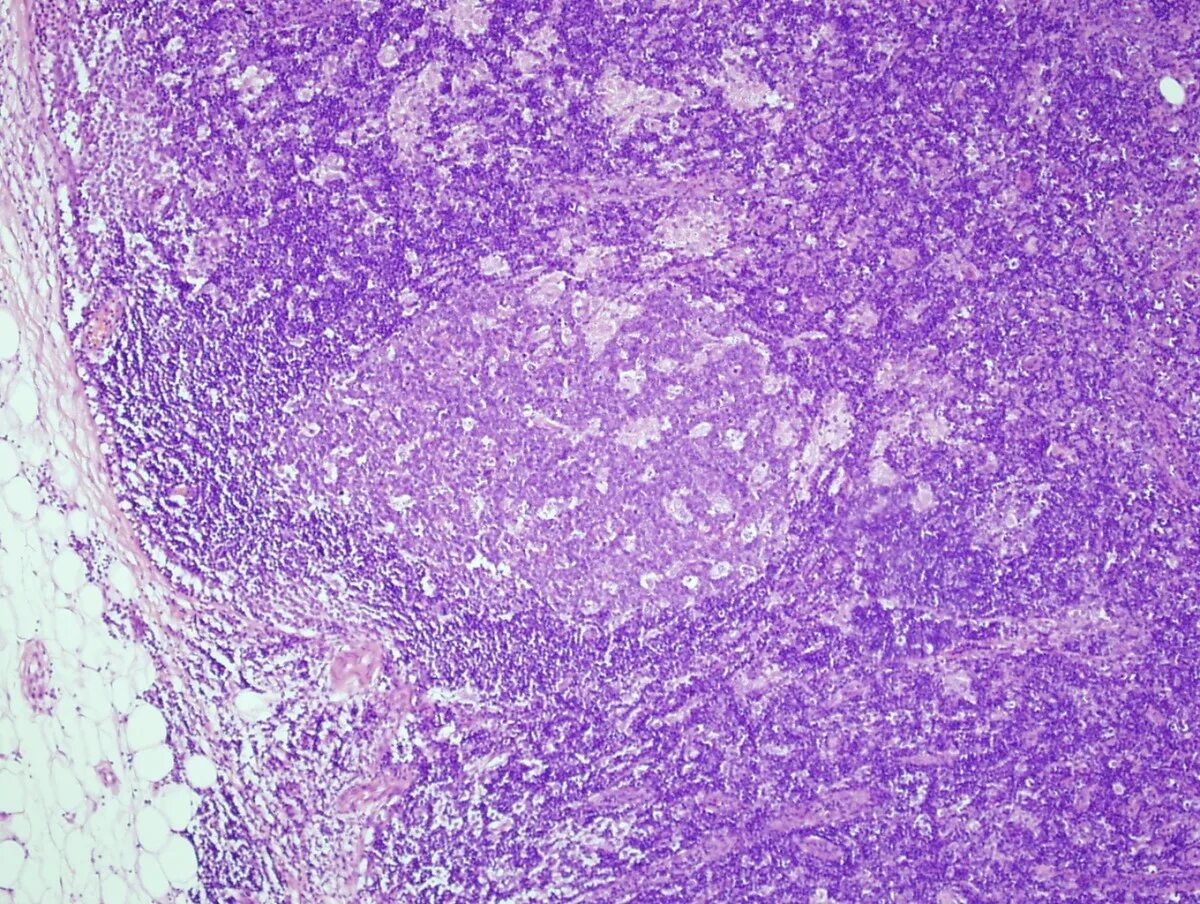

Эндометрит гистология